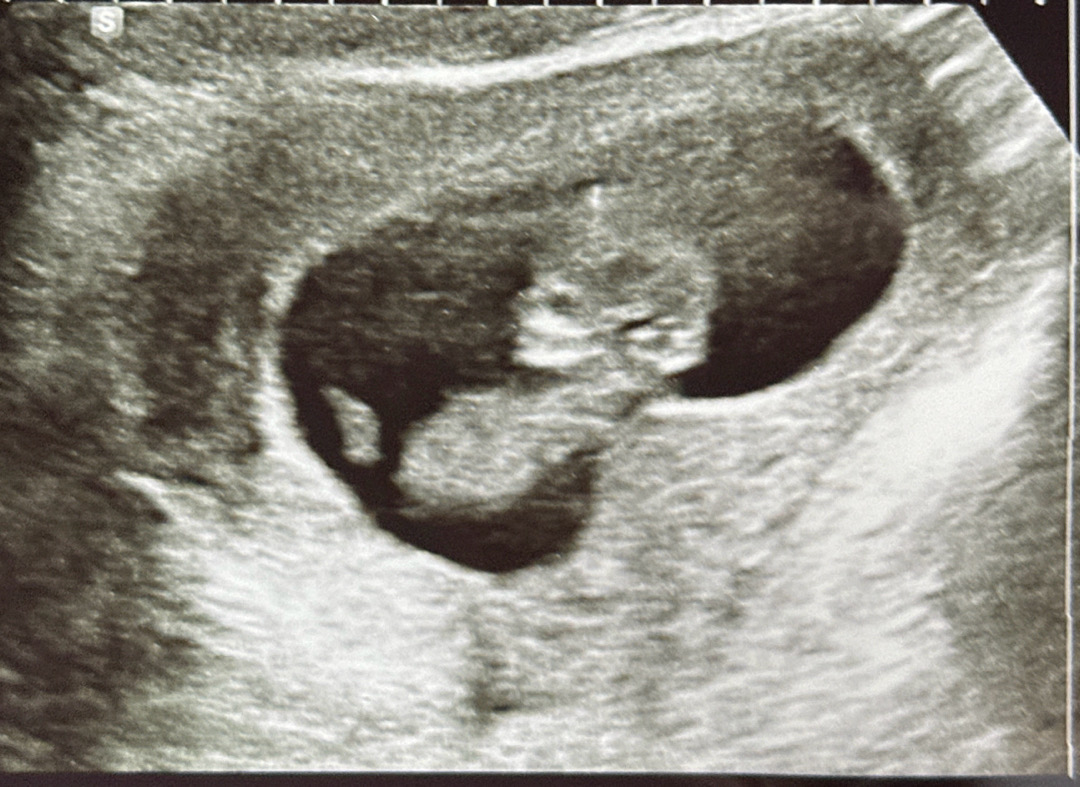

10주 5일 초음파

얼굴 생김새가 넘 적나라하게 보여서 놀랐어요..ㅋㅋㅋㅋㅋㅋㅋㅋㅋㅋㅋㅋㅋㅋㅋ 발차기랑 손도 흔드는데 넘 귀여웠어요 하루종일 서있고 뛰어다니고 무거운거 들고 스트레스받고 해서.. 매번 병원가기전에 애기 잘있을까 불안하고 궁금하고 한데ㅠ 잘있어줘서 넘 기특하네요^^ 2주를 또 어떻게 기다릴지ㅠㅠ 태동 언제쯤 느낄 수 있을지 ㅠ기다려져요 흑흑